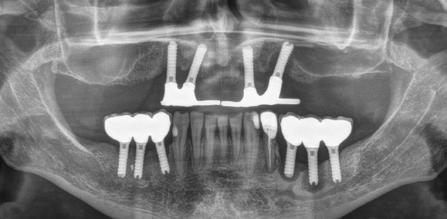

Retratamiento de un caso de periimplantitis de forma mínimamente invasiva. Extracción atraumática y confección de prótesis fija implantosoportada con carga inmediata. A propósito de un caso.

incisivo inferior proinclinado (Figura 7). La radiografía panorámica de inicio muestra 28 piezas dentales con terceros molares en formación con presencia del canino superior derecho impactado (Figura 8).